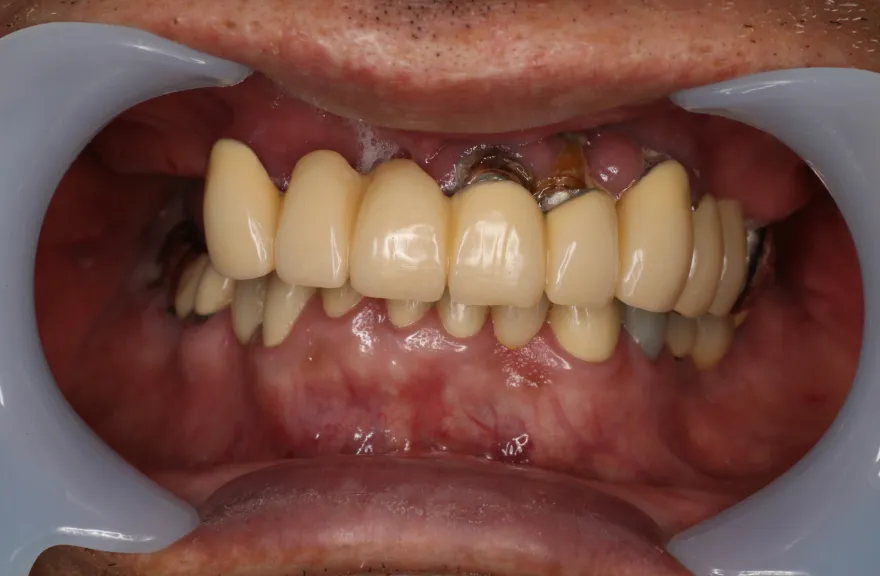

既にインプラント治療がなされており、使えるインプラントを使いながら足りないところにインプラントフィクスチャーを埋入し、噛み合わせを再構築する必要がある方でした。

上の前歯、右上の奥歯のインプラントはもう既に使える状態ではなく、また年月を経てすり減ってしまった下の前歯は噛み合わせを再構築する上で利用が難しい状況でした。

年齢を考えると、今回の治療で歯科治療を終えてしまい、残りの人生においてはメンテナンスのみで歯科へ通う状況を作りきってしまうことが求められました。

以上より、潔く残っている歯牙は抜去させていただき、上下をインプラントフィクスチャーによって固定式の歯を入れることとしました。 - 治療のリスク